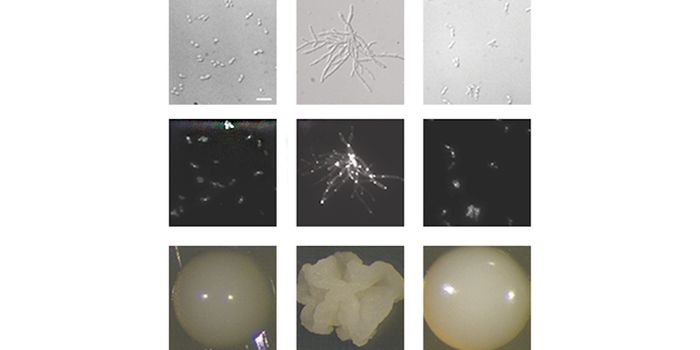

DEC 26, 2021Genetics & GenomicsCandida auris emerged as a pathogen around 2009, and has quickly become a serious problem for clinics and hospitals, whe ...

DEC 15, 2021MicrobiologyResearchers engineered a genetic circuit to make pathogenic bacteria called Myxococcus xanthus move in swirled patterns.

JUN 21, 2021MicrobiologyIn Brazil, clinicians have noted a rise in C. auris infections. Researchers believe that exhausted healthcare workers, o ...

MAY 28, 2021Genetics & GenomicsNew research assessed bacterial and fungal biofilms, tenacious microbial communities that are tougher than small groups ...

FEB 04, 2021MicrobiologyScientists have been able to grow Escherichia coli bacteria colonies in complex shapes that E. coli doesn't typically fo ...